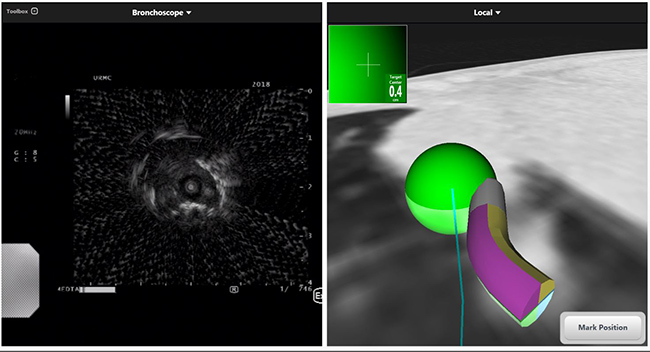

EBUS uses real-time ultrasound imaging to precisely biopsy even the smallest of lymph nodes along airways. Meanwhile, ENB is a powerful bronchoscopic technique using ‘GPS’-like technology to guide tools to more distant lesions in the lung for biopsy. ENB may be paired with radial endobronchial ultrasound to further enhance biopsy accuracy. URMC was a top enroller and active participant in the multi-center, international NAVIGATE study looking at patient outcomes with ENB, an experience our providers use to optimize care for our patients.